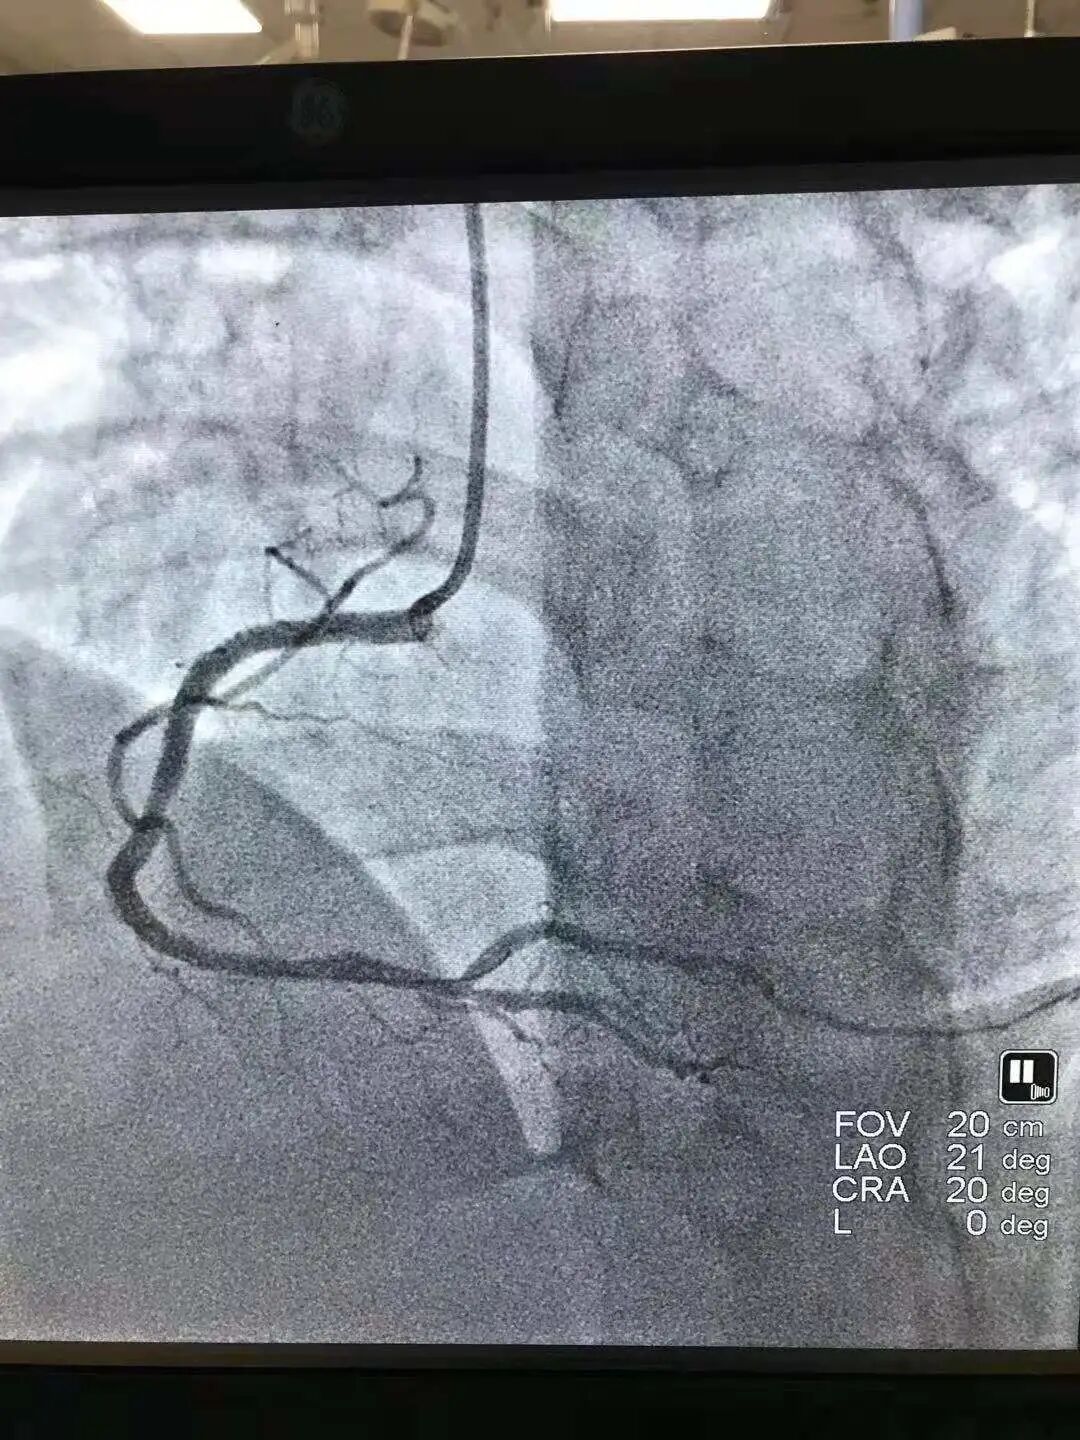

曲伟医生在造影中发现患者右侧冠脉完全闭塞,按照急症处理,给予冠脉介入治疗,迅速开通血管,从上手术台到手术结束不到40分钟,就成功把患者从死亡边缘拽了回来!

手术前